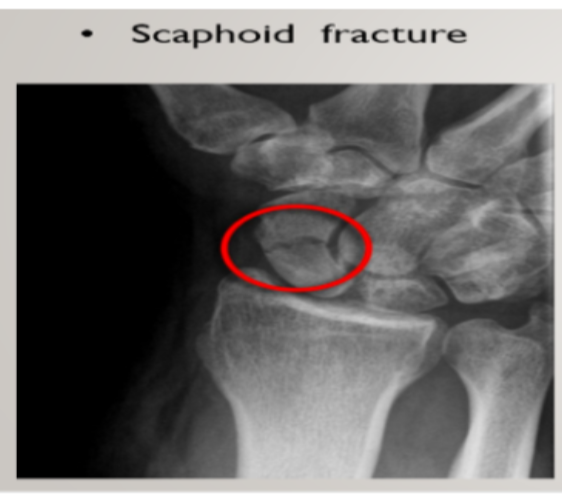

Name the common fractures in the Metacarpals and Phalanges (hand and finger bones)

A

1. Boxer’s fracture

2. Scaphoid fracture

Q

Which hand fracture commonly happens especially due to a fall

Scaphoid fracture

When a person falls, forces are transferred via

scaphoid bone —→radius –→ulnar—→ humerus

During a scaphoid fracture, there’s usually a lunate dislocation. Which nerve is compressed during this location?

Median nerve